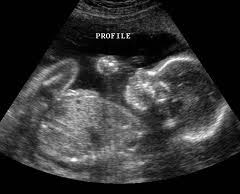

Prenatal Elective Limited Diagnostic Ultrasound Services

We provide prenatal elective limited diagnostic 3D, 4D scans to those expectant mothers who are currently receiving prenatal care, and have already undergone their diagnostic ultrasound.

We recommend having a 3D, 4D ultrasound performed between 24 and 34 weeks